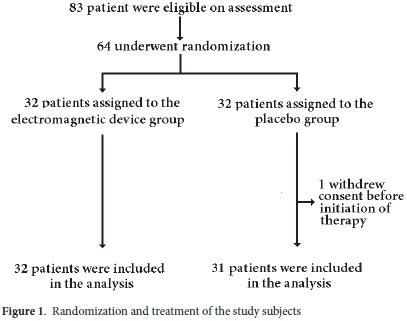

Eighty three patients fulfilled the eligibility criteria, 64 patients signed the consent form and were included. One patient withdrew consent, leaving a total of 63 participants. This is shown in Figure 1. Randomization was done six weeks after the day of fracture by using random numbers and allocating participants to either one of two groups: group A, assigned to the electromagnetic stimulation device, or group B, which received a placebo device, in a 1:1 ratio. Patients in both groups took the device to their homes where they were instructed on its use during one hour every day for eight weeks. Patients, physicians, and researchers were blinded and could not recognize between real-devices and placebo-devices. A technician installed the device at home and taught the patient and relatives how to properly use the device. Every day, each patient received a call from a health-care worker asking if they had used the device, at what time and for how long, as a way to check and improve adherence to the therapy. Every week, a technician visited the patients, calibrated the device, and checked for how long the therapy was done in the device record.